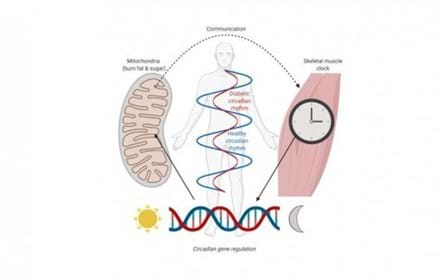

Diabetesmedicin kan fungera som ”träningspiller”

Når mitokondriene ikke kan holde styr på tiden

Muskelgen kopplas till typ 2-diabetes

Gåtan med metabola minnet förklarad?